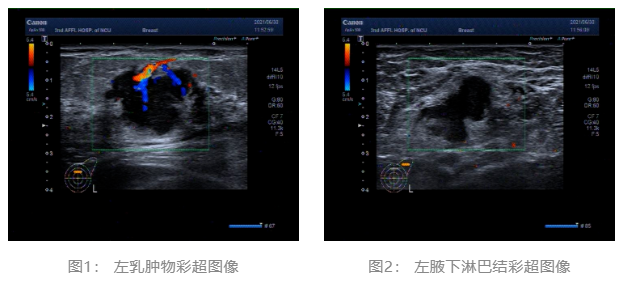

2021.06.30 乳腺彩超:左侧乳腺低回声团块,BI-RADS-US 4c类。左侧腋窝肿大淋巴结。(图1、2)